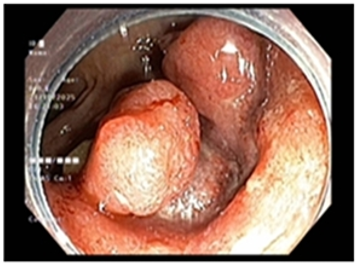

UNG THƯ DẠ DÀY KHỞI PHÁT SỚM

Theo Globocan 2022, ung thư dạ dày đứng thứ 5 về tỷ lệ mắc và tỷ lệ tử vong, với 968 784 ca mắc mới và 660 175 ca tử vong. Bệnh tiến triển thầm lặng, các triệu chứng ban đầu  thường mơ hồ và không đặc hiệu dễ nhầm lẫn với các bệnh lành...